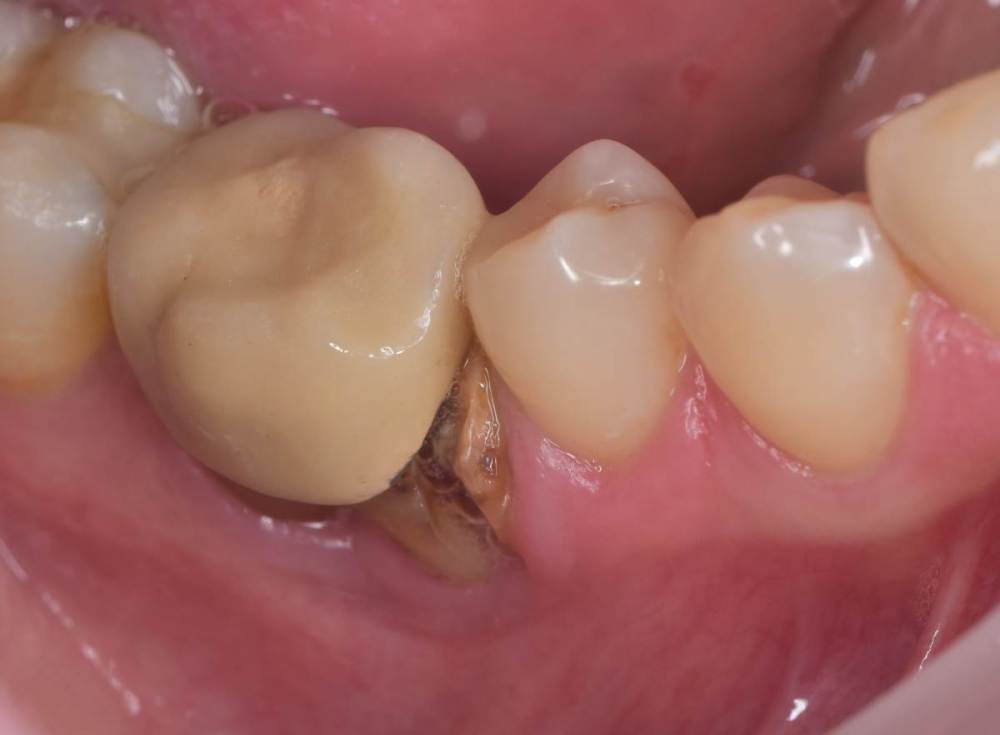

TIGER Опубликовано 14 июля, 2023 Автор Поделиться Опубликовано 14 июля, 2023 всем привет!Не всегда одномоментная имплантация метод выбора,в данном кейсе пошёл по более прогнозируемому пути для сохранения тканей 1 1 Ссылка на комментарий

Doc Опубликовано 14 июля, 2023 Поделиться Опубликовано 14 июля, 2023 7 часов назад, TIGER сказал: всем привет!Не всегда одномоментная имплантация метод выбора,в данном кейсе пошёл по более прогнозируемому пути для сохранения тканей И очень неплохо получилось 1 1 Ссылка на комментарий